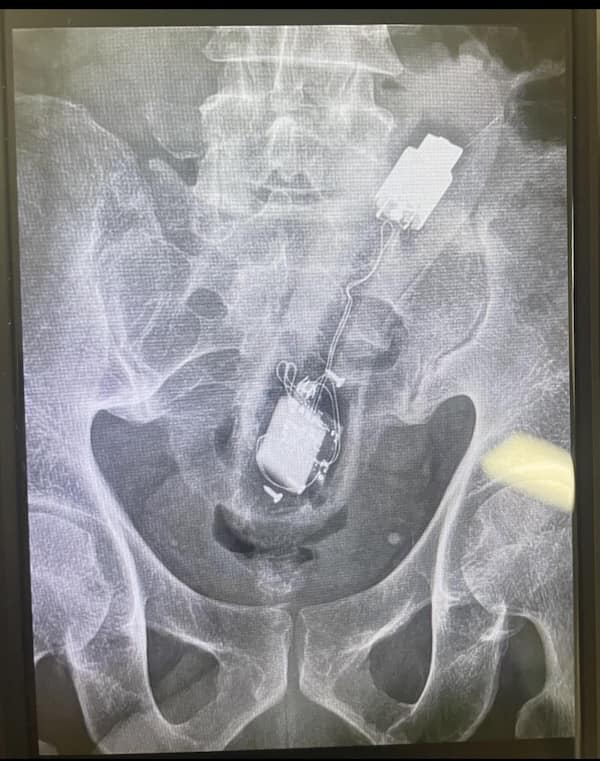

I used to think that nothing could surprise me anymore—until I stumbled upon some weird x-ray photos that made me reconsider my stance on human ingenuity (or lack thereof). Apparently, some people have a knack for getting objects lodged where they absolutely shouldn’t be. If you’ve ever wondered how not to use everyday items, these images might provide some unintended guidance.

This collection showcases 31 bizarre x-ray images that defy logic and anatomy textbooks alike. Each photo reveals unexpected objects making cameo appearances inside the human body, turning medical imaging into a gallery of the absurd. From common household items inexplicably found in unusual places to anomalies that would leave even seasoned doctors scratching their heads, these images offer a perplexing glimpse into the more “creative” side of medical emergencies. They highlight the intersection of curiosity, misadventure, and perhaps a dash of poor decision-making, all captured through the lens of radiology.